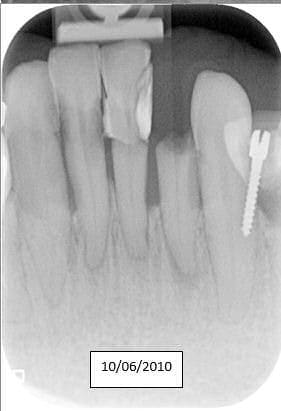

docgentil

04/05/2016 à 18h13

Le Screw du jour.

Ce qui m'attriste le plus c'est que le patient a 25 ans.

Sc33 bczylk - Eugenol